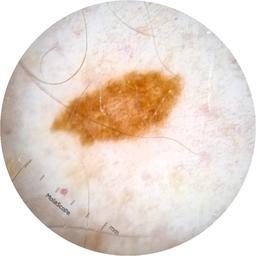

ISIC_6813604

MEL-SELF Trial, https://www.sydney.edu.au/medicine-health/our-research/research-centres/melself-project.html

acquisition_day 624

age_approx 75

anatom_site_1 Head and neck

anatom_site_general head/neck

diagnosis_1 Benign

diagnosis_confirm_type single image expert consensus

fitzpatrick_skin_type I

image_type dermoscopic